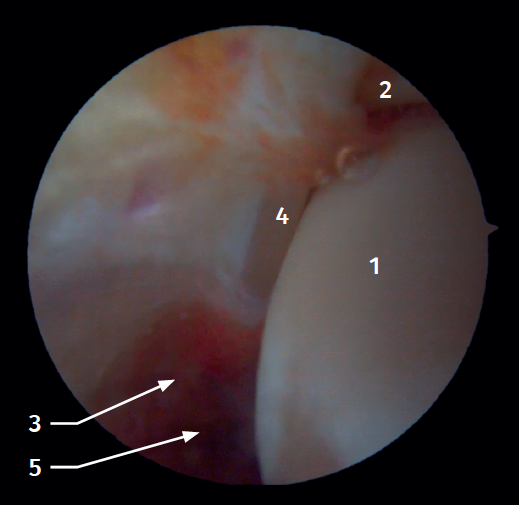

Figure 2. Anterolateral arthroscopic view of the right ankle. 1: talar dome; 2: anterior aspect of the tibia; 3: fibula; 4: distal fibers of the anterior tibiofibular ligament; 5: anterior talofibular ligament.

Twenty percent of the ATFL is intra-articular(7). On adopting an anteromedial access of the ankle, directing the arthroscope laterally, we can see the distal fibers of the ATFL with their oblique distribution and their continuation with the anterior talofibular ligament (Figure 2). If we move into the tibiotalar joint, we see the distal tibiofibular joint with the syndesmotic recess occupied by synovial tissue (Figure 3).

Arthroscopic anatomy of the medial complex

Arthroscopy allows us to see the deep fibers of the deltoid ligament, corresponding to the intra-articular portion of the ligament. Medial and proximal to the tip of the malleolus we have the insertion of the deep layer of the deltoid ligament. If there is no injury, we will see the anterior portion of the deep tibiotalar fibers. When injury is present, we can visualize the intermediate and posterior portion. The superficial bands, due to their more external location, are not visible by arthroscopy, unless there is no lesion of the deep bands (Figure 5).